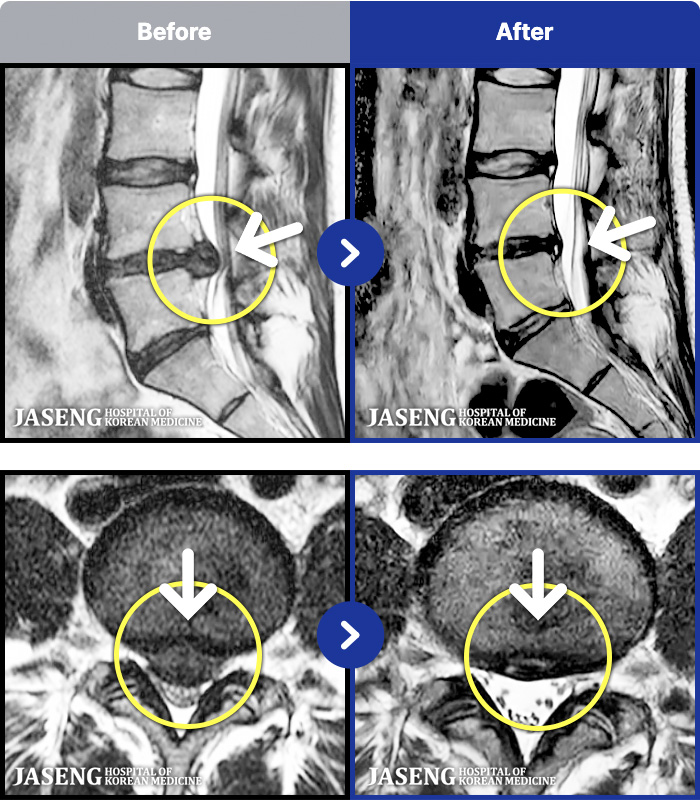

MRI ġ

1,301 MRI ũ ʸ Ȯϼ.